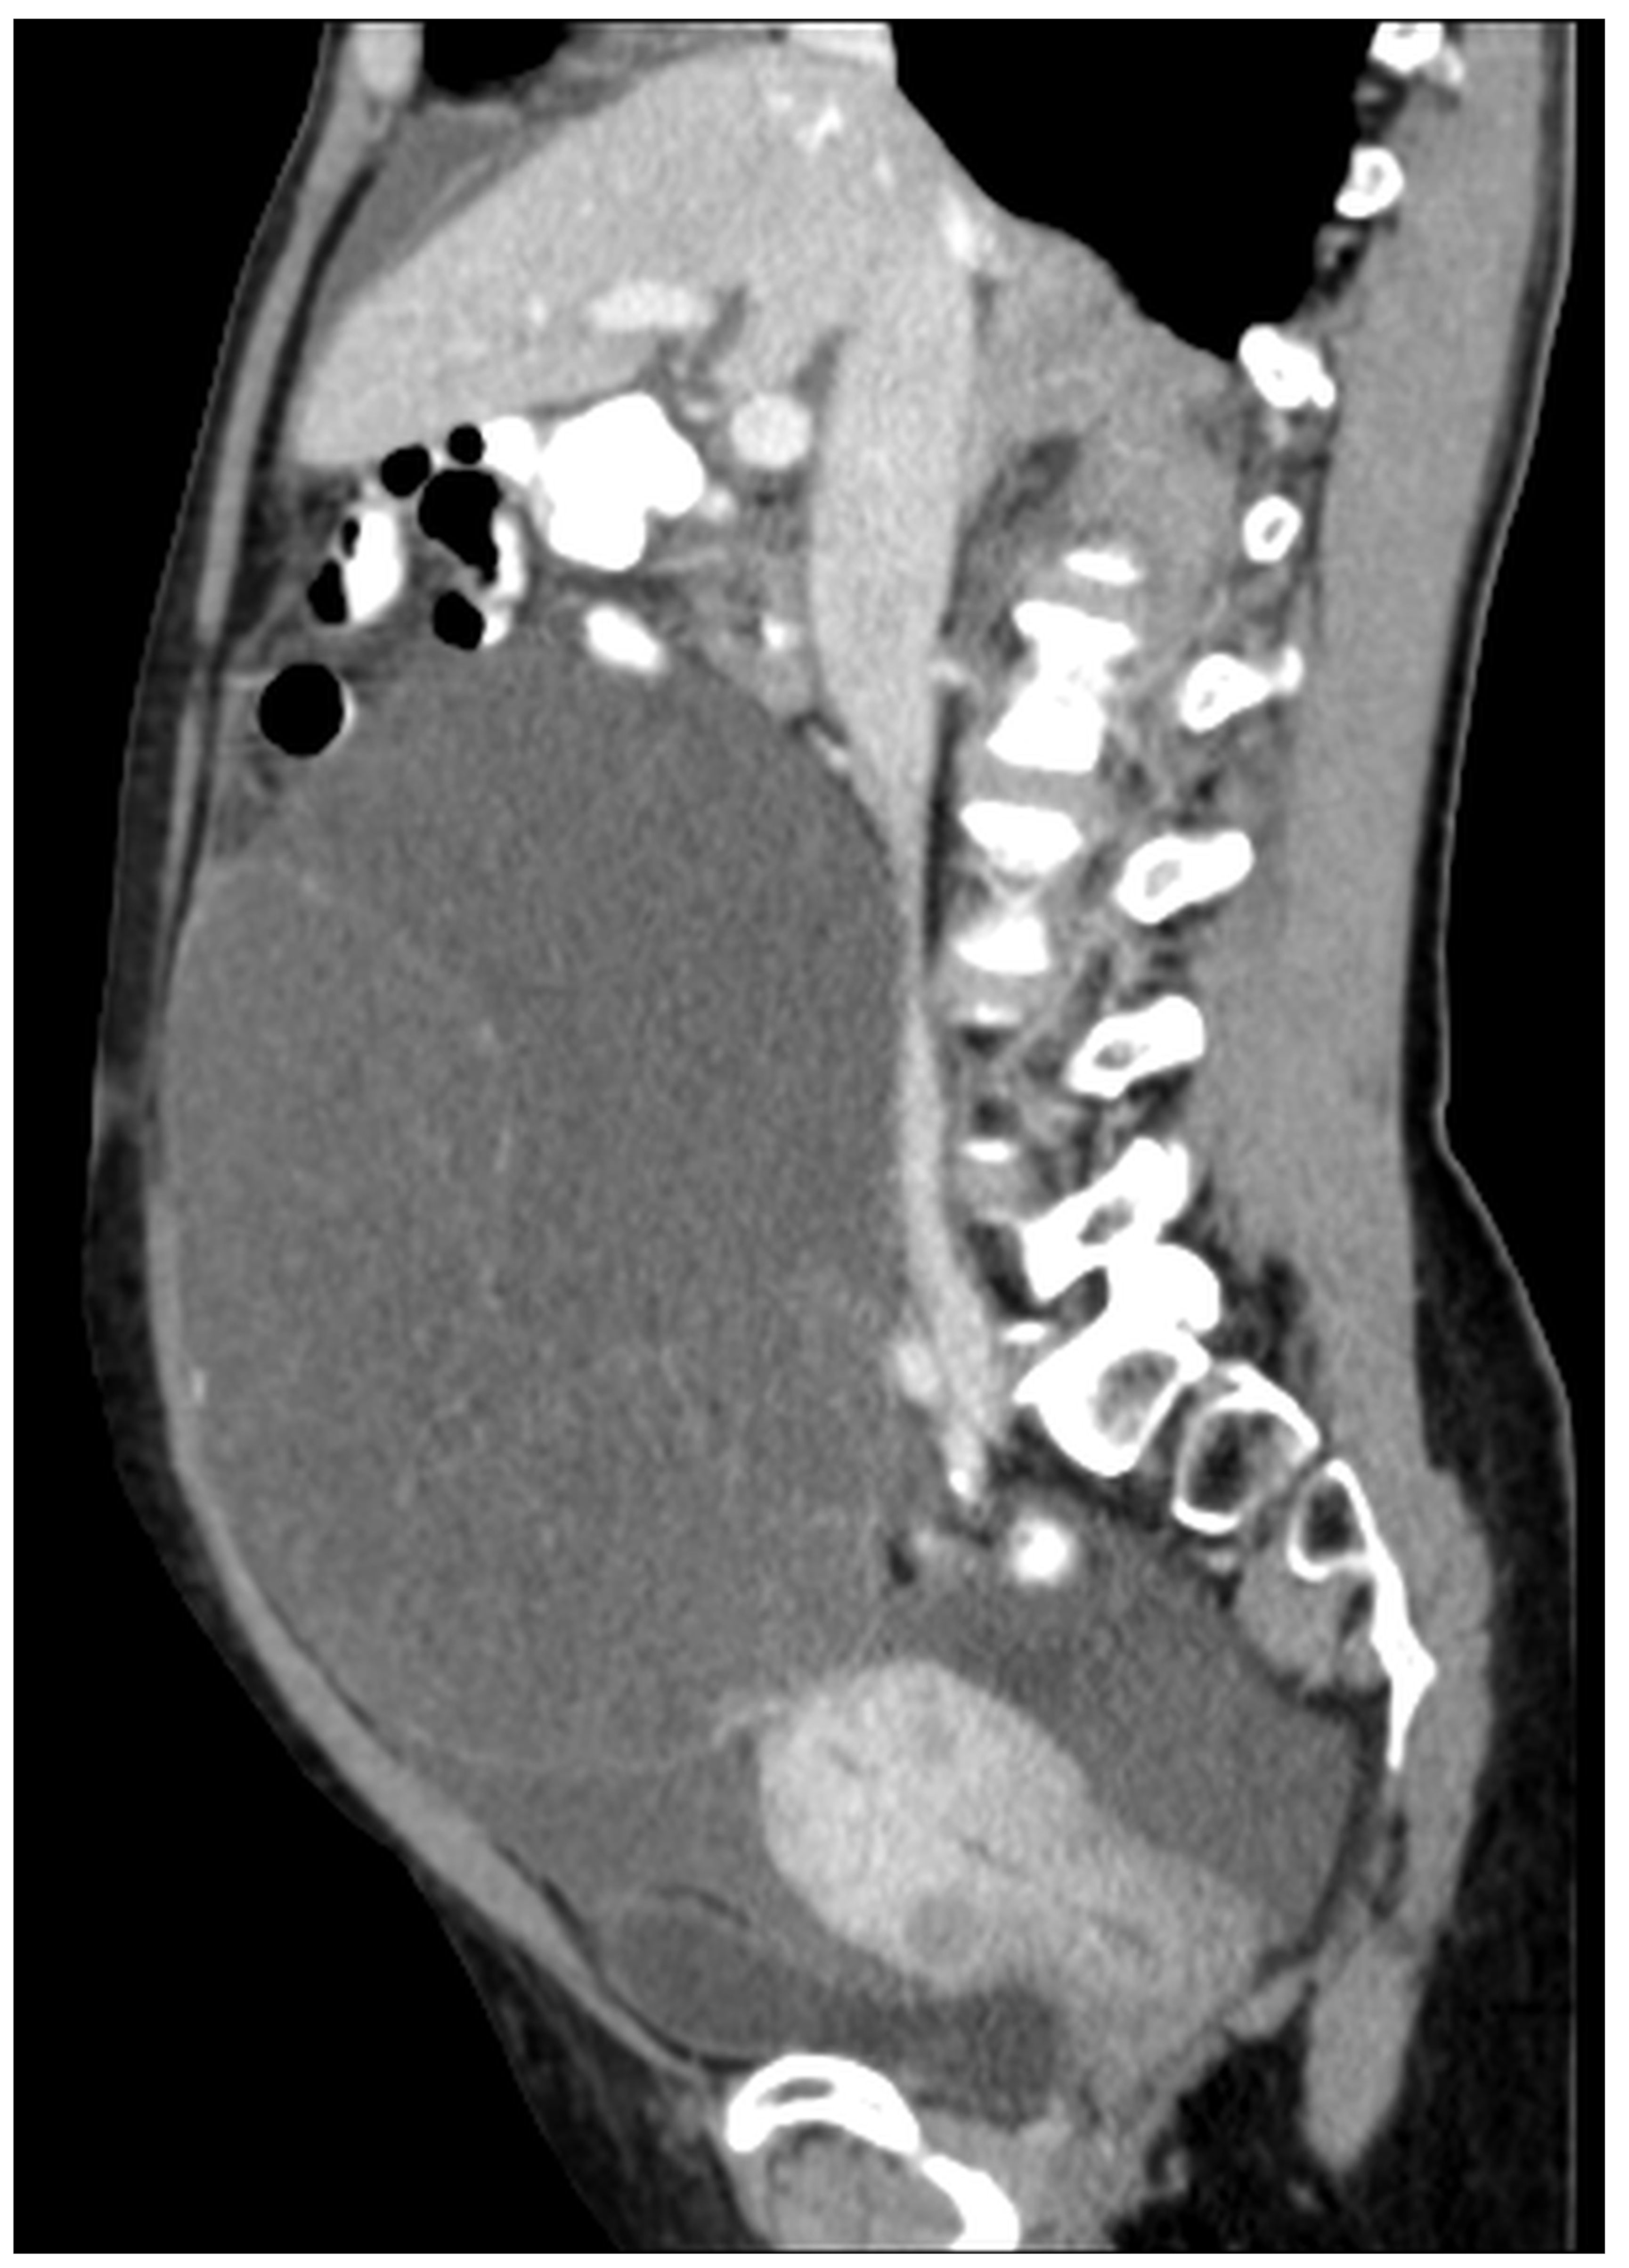

Figure 15. CT, venous phase, sagittal plane.

Figure 11, Figure 12, Figure 13, Figure 14 and Figure 15. Advanced stage of the disease. The abdomen is full of tumors and mucin. Typical signs are heterogeneous or hypodense masses in the form of lobules often with septa, which could be enhanced by contrast and could be associated with calcifications.

Patients with a misdiagnosed rupture of the mucocele may develop pseudomyxoma peritonei. It is characterized by the presence of an abundant gelatinous substance in the abdomen. Diffuse, progressive, and abundant mucin-containing tumor cells are typical of this disease [2] (Figure 11, Figure 12, Figure 13, Figure 14, Figure 15 and Figure 16). The interval between rupture and advanced disease is several years. In our clinical series, the interval was about 5 years. In the literature, we found a wide range of this interval from 12 months to 10 years [9,10]. The natural history of PMP revolves around the “redistribution phenomenon”, whereby mucinous tumor cells accumulate in the Douglas pouch, in the diaphragm (more on the right), and the small and large omentum (Figure 17). The small intestine is less involved [4]. Pseudomyxoma peritonei is a slowly progressing disease, which fills the peritoneal cavity over time. There are several classifications of pseudomyxoma. The most commonly used is the PSOGI classification [2]. Mucinous accumulation progresses to malnutrition, bowel obstruction, and respiratory compromise. Rarely, the tumor may spread to the pleural cavity. This has been described in 5.4% of cases. It may occur spontaneously or as a result of diaphragmatic injury during cytoreduction [8,11].